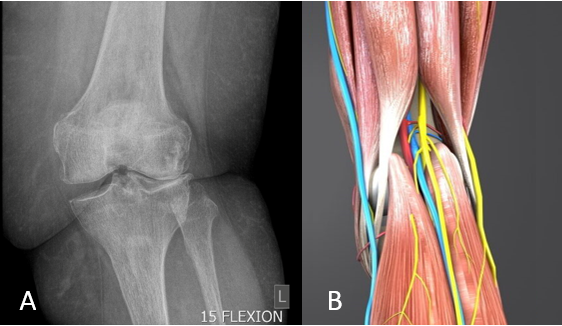

Figure 1. On the left (Image A), a knee radiograph of an individual with obesity shows poor joint alignment, increasing load on the lateral (outer) compartment — a biomechanical setup that can accelerate joint degeneration. On the right (Image B), a posterior view highlights the muscles that support the knee, helping maintain alignment and reduce shear forces across the joint.

OA is often diagnosed too late. We showed that clinical criteria — like the Criteria for the Early Diagnosis for Knee OA (CREDO) models developed by Erasmus University — can detect OA before it appears on X-rays. In collaboration with GLA:D®, we found that early-diagnosed patients improved significantly with existing treatments.